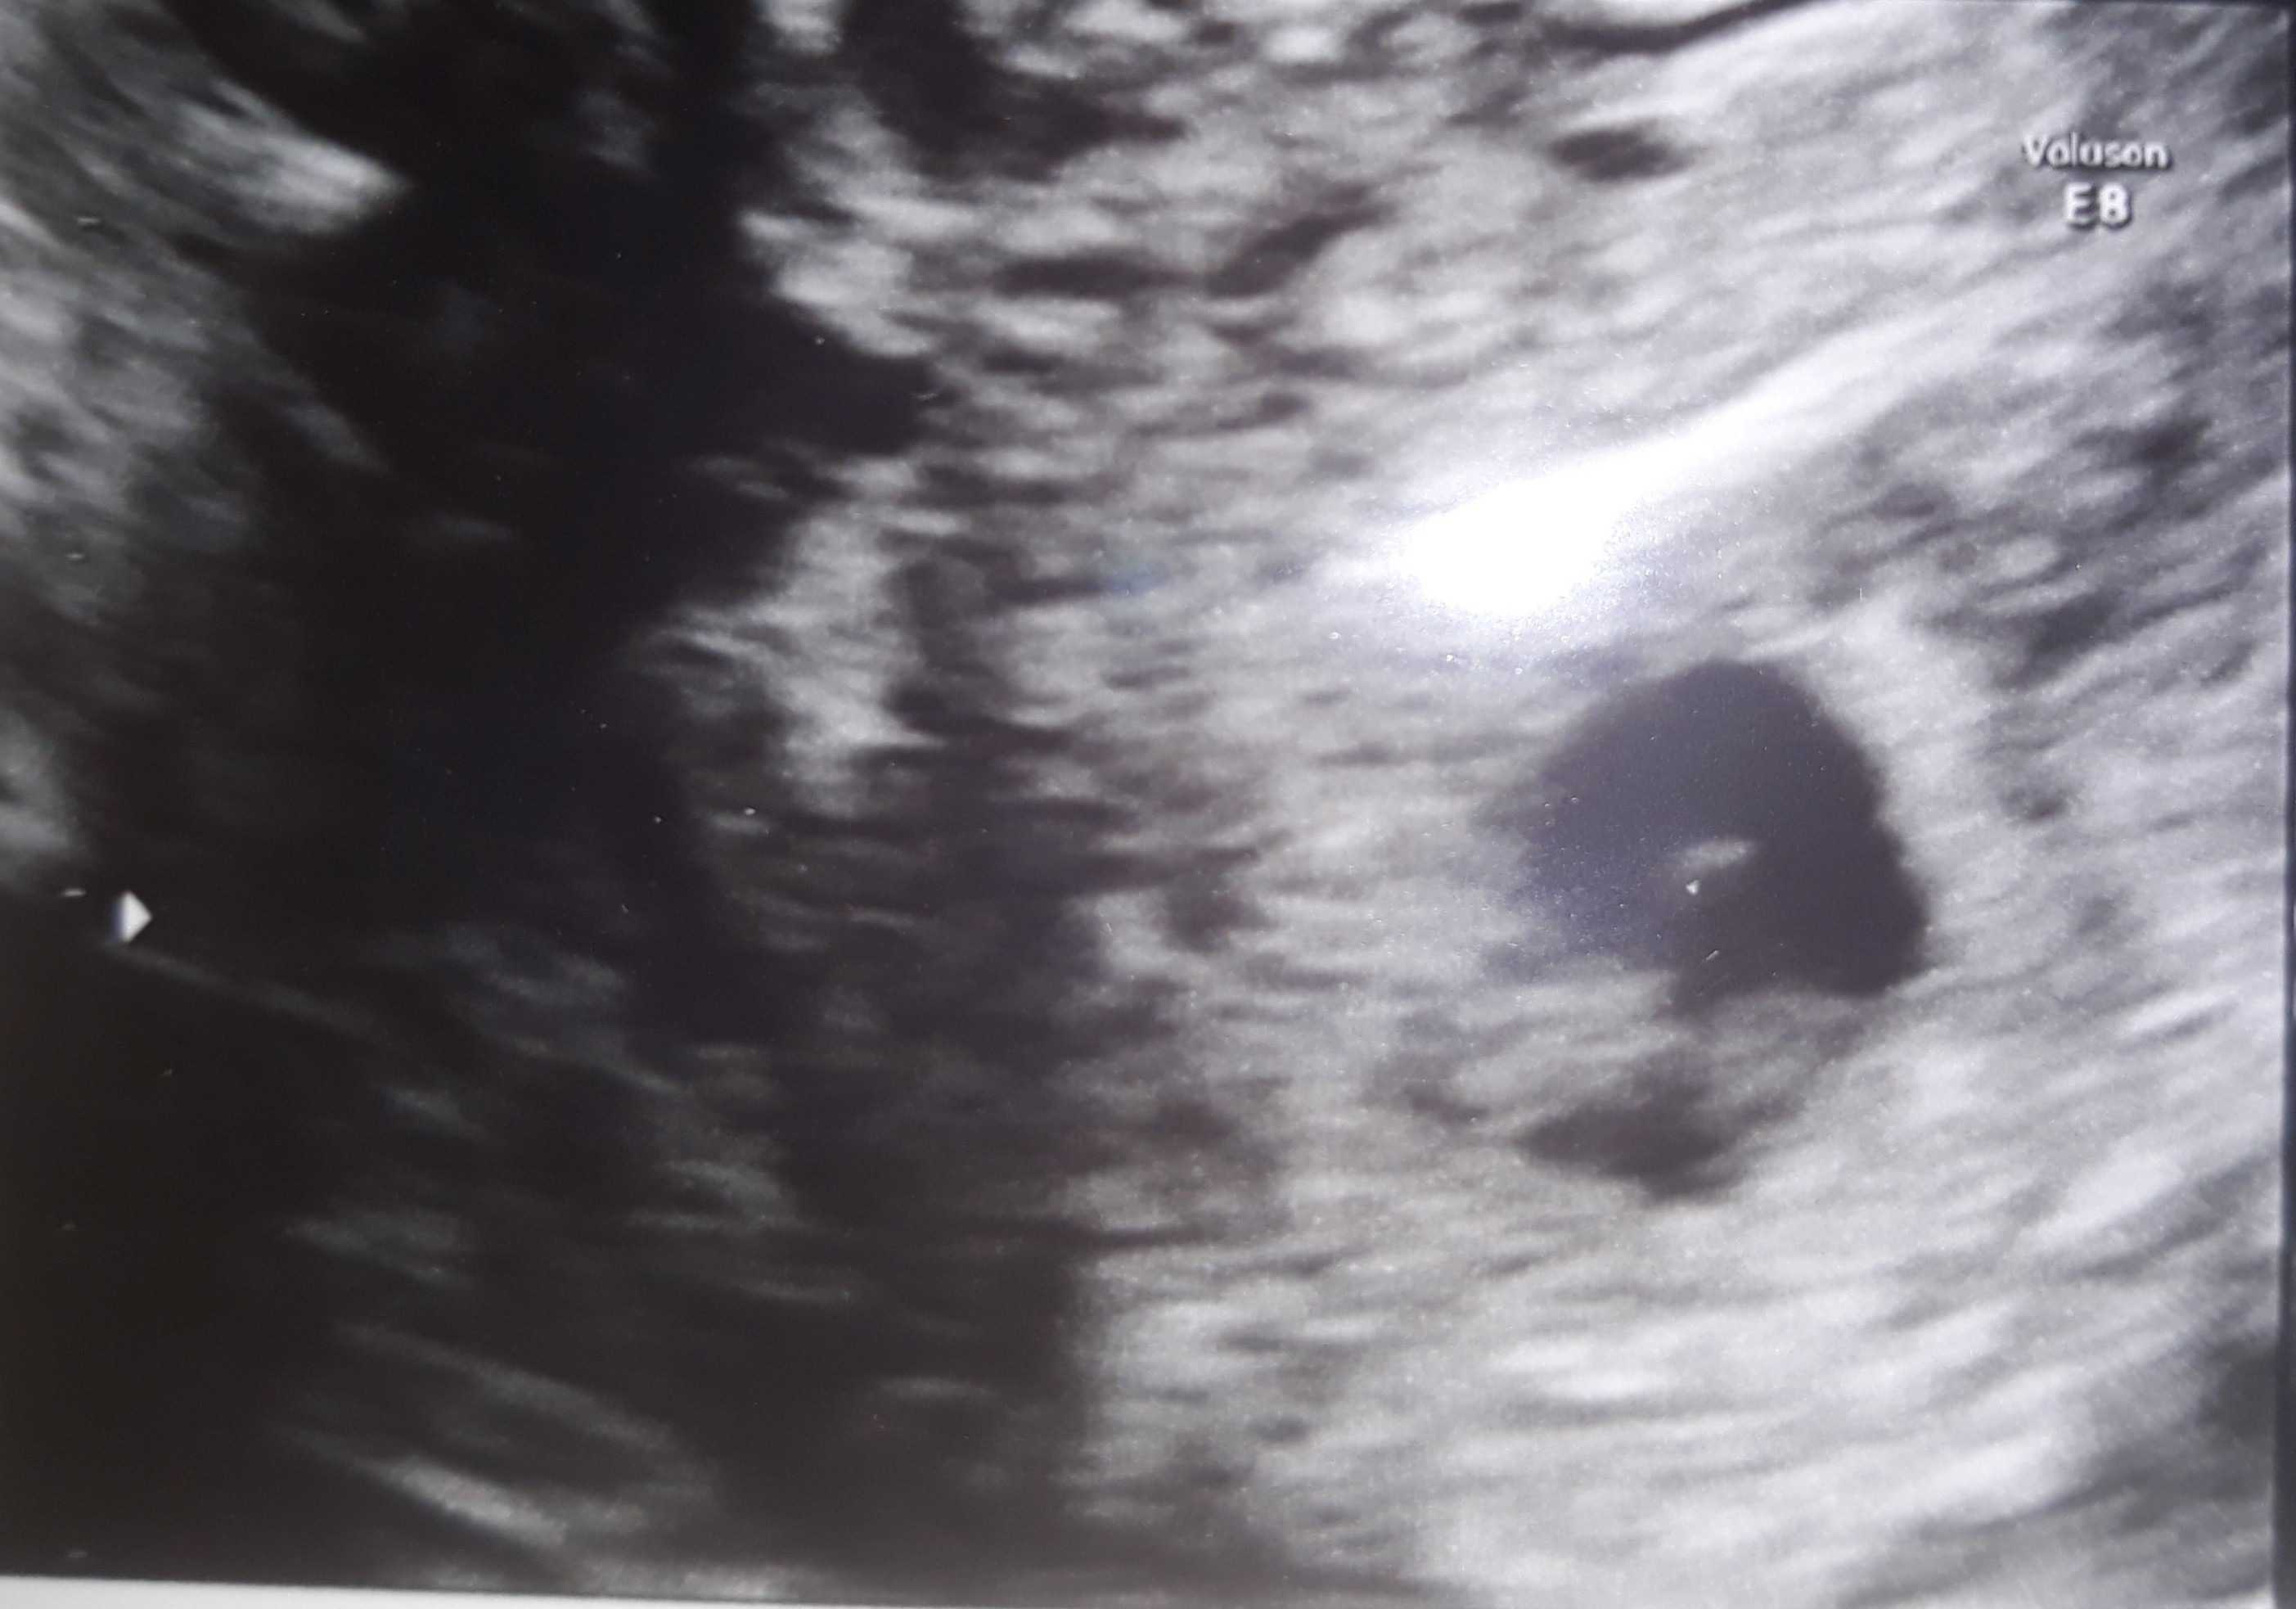

5 tydzień, nieregularny pecherzyk ciążowy

To moja 4 ciąża, poprzednie 3 straciłam. Teraz od razu od pozytywnego testu zaczęłam brać heparynę drobnoczasteczkową. Dokładnie w dniu spodziewane miesiączki miałam brązowe plamienie, jednorazowe, bez żadnego bólu. Do ginekologa poszłam w 5 tygodniu, na usg pęcherzyk uwidoczniony w macicy, ale... jego kształt jest nieregularny. Brzegi nie są równiutkie, nie jest to idealne kółko. Miałam zrobić bete w odstępie 48 godzin, pierwsza już za mną 7140, więc 5-6 tydzień.

To są zdjęcia mojego nieregularnego pęcherzyka.

Załączniki

• 20210417_113548.jpg

20210417_113548.jpg

496,3 KB · Wyświetleń: 1 271